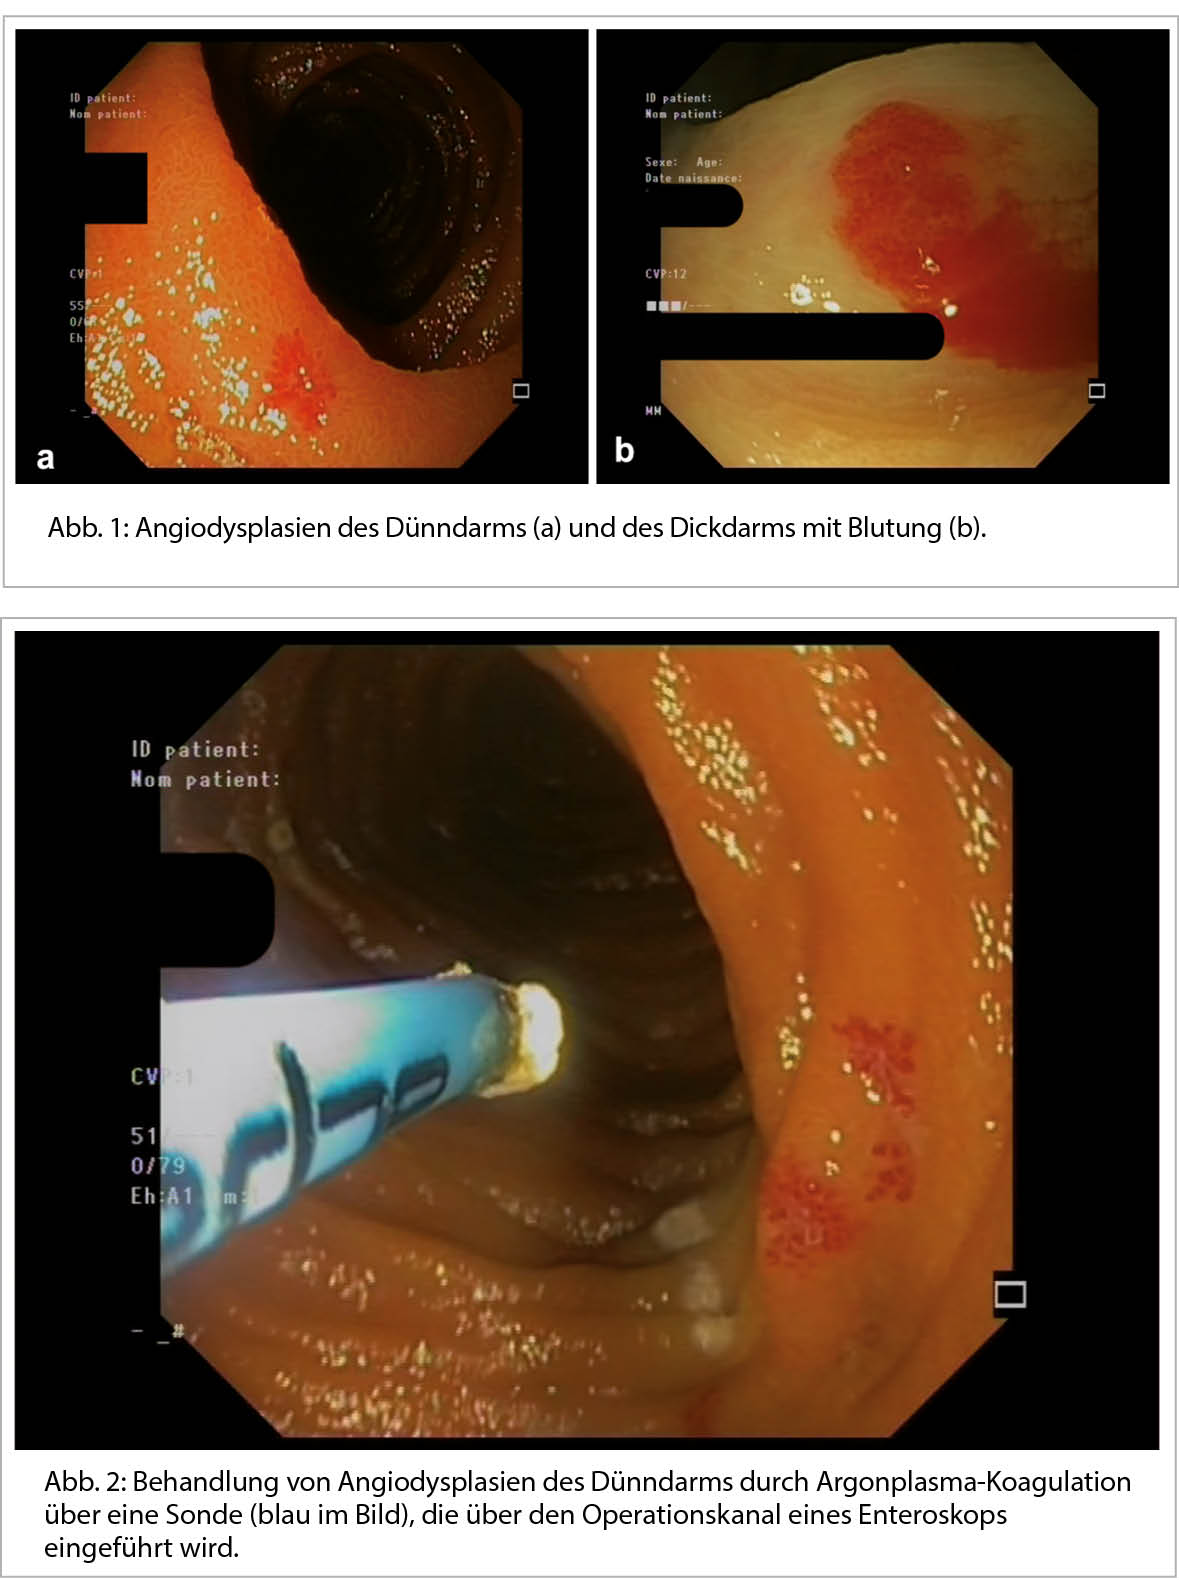

Die gastrointestinale Angiodysplasie ist eine meist erworbene, manchmal auch angeborene Anomalie im Zusammenhang mit der Rendu-Osler-Krankheit. Es handelt sich um einen degenerativen und ischämischen Prozess, der sich zu einer venösen Stauung entwickelt. Die Angiodysplasie tritt in Form einer oberflächlichen, meist kleiner als 1 cm grossen vaskulären Läsion auf, die sich in der Schicht der Mukosa oder der Submukosa entwickelt hat. Sie tritt als rote, manchmal leicht erhabene Läsion mit unregelmässigen Konturen auf (Abbildung 1).

Die Behandlung erfolgt in erster Linie endoskopisch. Die Standardbehandlung ist die Argonplasma-Elektrokoagulation, eine thermische Methode zur Blutstillung, bei der ionisiertes Argon über eine Sonde versprüht wird (Abbildung 2).